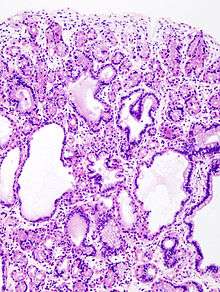

H&E stain of fundic gland polyp showing shortening of the gastric pits with cystic dilatation

The polyps on endoscopy are usually tiny, numerous and sessile,[3] and usually scattered throughout the fundus of the stomach, where parietal cells are more numerous. They have the same colour as the gastric mucosa, and never have a stalk.[4] When the polyps are biopsied, the pathology typically shows shortened gastric pits, and both superficial and deep cystic lesions in the fundic glands, lined by all three types of cells of acid-producing mucosa: mucous, parietal and chief cells. As sometimes parietal cell hyperplasia may develop deep dilations of gland,[5] one should be really strict in the diagnosis of FGPs (i.e. the presence of deep and superficial dilations). Infrequently, the two lesions may coexist.[3] Foci of dysplasia can sometimes be seen.[4]